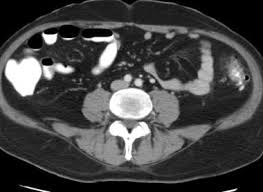

Mri scan > pet scan > ct scan > pregnancy ultrasound scan > other scans and investigations > find the cost of. An mri, by the very nature of the procedure, does not pose any radiation risk. Ct scans can produce detailed images of many structures inside the body, including the internal organs, blood vessels and bones. How much does a ct scan cost? On mdsave, the cost of a ct scan with and without contrast ranges from $320 to $1,869.

Read more about how mdsave works. Ct scans allow physicians to rapidly create detailed pictures of the body allowing them to more easily diagnose problems such as cancers, cardiovascular disease, infectious disease, trauma and musculoskeletal disorders. $10,174.75, including $8,897 for a ct scan of the abdomen. About 100 ct scans pose a high risk of cancer. In new york city, the total cost—including. 5%, more than 22 scans; A ct scan (also called a cat scan) is a noninvasive, painless medical test that helps physicians diagnose and treat medical conditions. Scans that require the injection of iodine, for instance, could run up to $1,000 for the entire procedure.

The average cost of a ct scan in the united states is $3,275, though prices can range from $300 to $6,750. Costs may also vary by veterinarian and geographic location. Ct scans are quick, painless and generally safe. For the group as a whole, the increase in risk was slight — 0.7% above the overall lifetime risk of cancer in the united states, which is 42%. An mri, by the very nature of the procedure, does not pose any radiation risk. How much does a ct scan with and without contrast cost? How much does a ct scan cost? Mri scan > pet scan > ct scan > pregnancy ultrasound scan > other scans and investigations > find the cost of. In new york city, the total cost—including. With a ct scan, the machine. How much do ct scans for pets cost? Read more about how mdsave works. Ct scans are sometimes called cat scans.